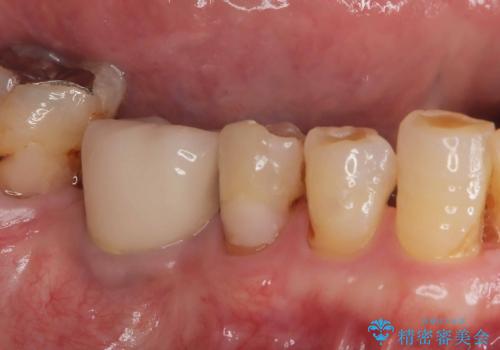

- 虫歯が原因で歯が欠けていました。昔詰めた保険の材料(CR)が劣化しその下が虫歯になっている状態でした。

色々な箇所にCR(保険の材料)を詰めてあったので、CRと虫歯を全部除去した後、オールセラミッククラウンで治療を行いました。

- 132,000円(仮歯:10,000円+オールセラミッククラウンスタンダード110,000円)費用は治療当時の料金となります

古いCR(保険治療で使用されるプラスチック)を除去すると残りの歯質が薄いため、破折抵抗を考慮しオールセラミッククラウンで治療を行いました。